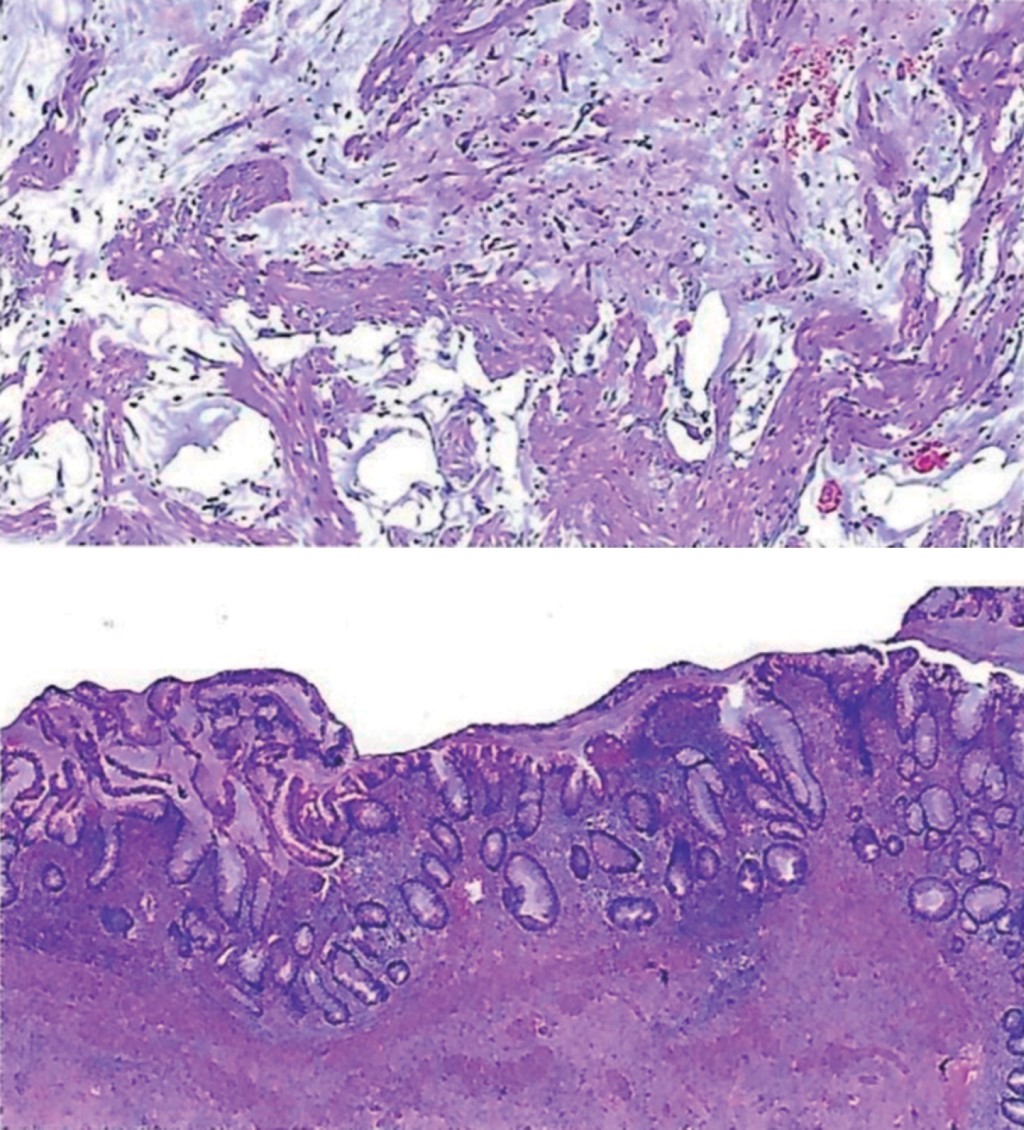

Se toma pieza quirúrgica y se envía a patología (Figura 3).

Reporte de patología 06/12/22: neoplasia mucinosa del apéndice cecal rota e inflamación aguda intensa pseudomixoma peritoneal secundario. El reporte recomienda estudio de inmunohistoquímica para confirmar diagnóstico y descartar malignidad (Figura 4).

Reporte de inmunohistoquímica 13/12/22: CKAE1/AE3 negativo, CK20 negativo, CK7 negativo, MUC5 negativo. Diagnóstico: tumor mucinoso con apendicitis aguda y adenomucinosis, probable cistoadenoma mucinoso.

Figura 3

Figura 4